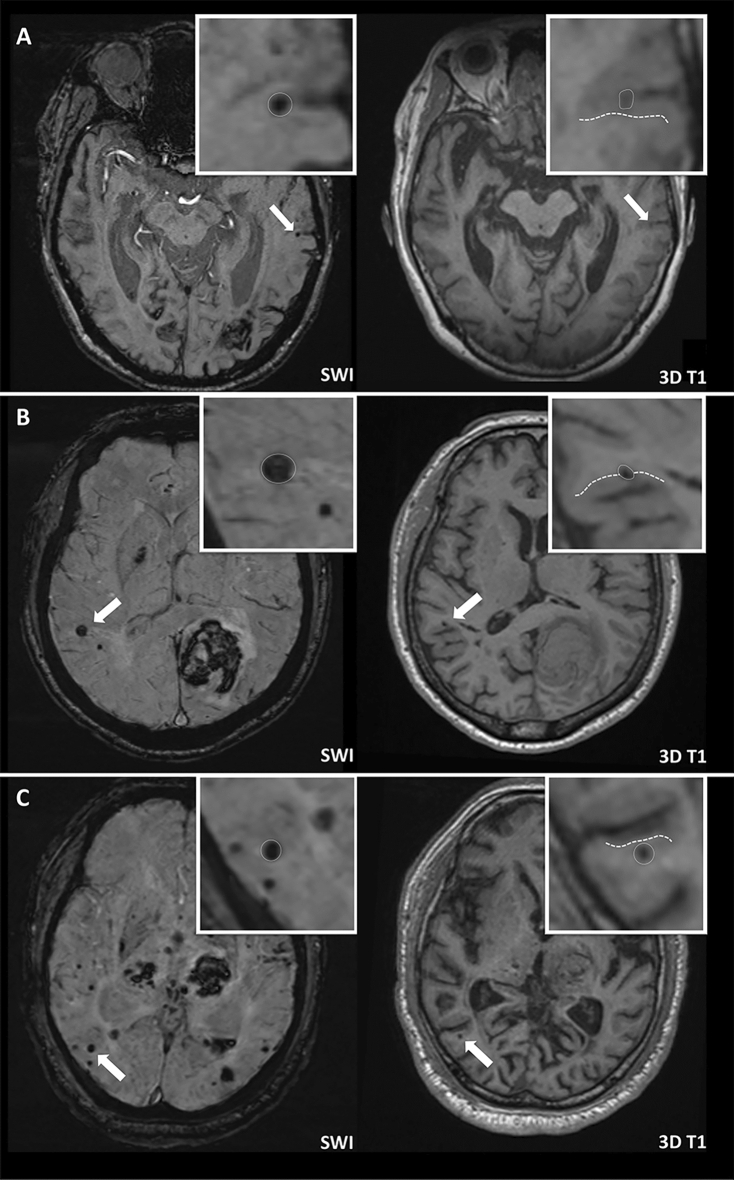

Each lobar CMB was first identified by reviewing SWI sequences. However, due to the limitations of SWI with respect to anatomical discrimination, lobar CMBs were further categorized as intracortical, juxtacortical, or subcortical based on their relative location to the cortex using the corresponding T1-weighted multiplanar reconstruction images, as shown in Fig. 2. Intracortical CMBs were defined as CMBs completely located in the gray matter of the cortex (Fig. 2A); juxtacortical CMBs were defined as CMBs located on the border of gray-white junctions (Fig. 2B); subcortical CMBs were defined as lobar CMBs located in the white matter without reaching the cortex (Fig. 2C). Strictly intracortical/juxtacortical lobar CMBs were defined as having no lobar CMB in the subcortical white matter. All MRI scans were independently rated by two investigators (P.-Y. K., 3-year reading experience and P.-T. C., 6-year reading experience) to determine the inter-rater reliability for the presence/absence of intracortical and subcortical CMBs. If there was disagreement between the two readers, the same investigators reached a consensus decision after discussion.

Figure 2.

Categorization of lobar CMBs. The location of each lobar CMB was categorized using SWI and the corresponding 3D T1-weighted images. (A) Intracortical CMB: the lobar CMB is completely located in the gray matter of the cortex. (B) Juxtacortical CMB: the CMB is located on the border of a gray-white matter junction. (C) Subcortical CMB: the CMB is completely located in white matter. The borders of the cortex are outlined with dotted lines.